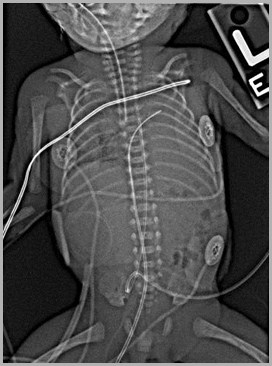

UAC at T5UVC probably in left atrium or pulmonary vein

5

UVC in left atrium

Auckland